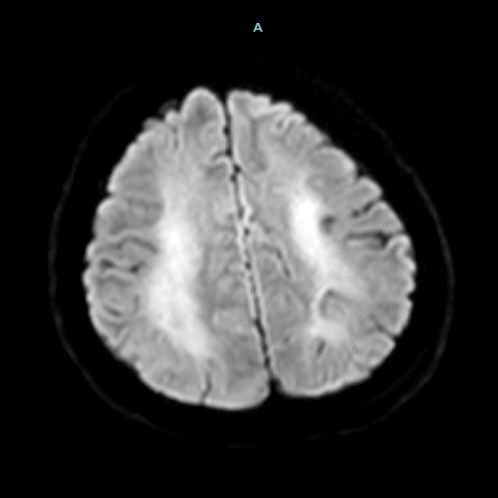

66 yaş, E

Kardiak arrest, 10 dk CPR öyküsü